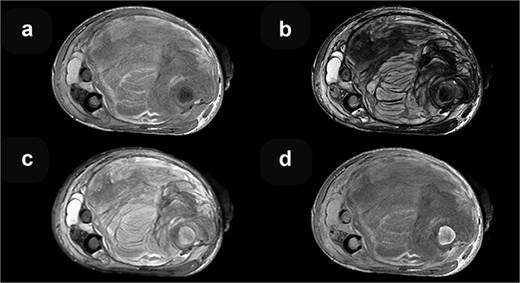

MRI axial sequences of the femur at the level of the fracture reveal a heterogeneous soft tissue mass. This mass exhibits predominantly iso-hyperintense signals on T1-weighted images (a), which, when correlated with T2-weighted images (b), are consistent with a hematoma of varying ages. The surrounding bone demonstrates normal signal intensity on T2 FS (c), and T1 contrast-enhanced (d) sequences.

Coronal T1-weighted (a) and post-contrast T1-weighted (b) MRI sequences demonstrate no discernible contrast enhancement within the mass.